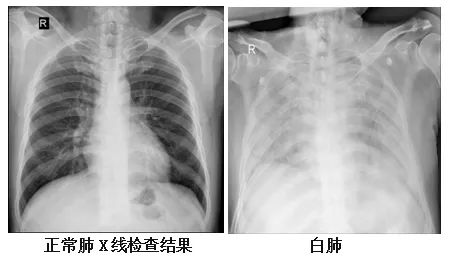

复旦大学附属华山医院感染科副主任医师张继明介绍,正常情况下,肺部主要是由充满了空气的肺泡组成,进行CT或者是X线检查时,射线可以很容易地穿透肺泡,在影像学上显示为黑色区域;当肺部受到病原体感染、临床上表现为重型肺炎时,患者肺泡里会出现炎症、渗出或实变时,射线不容易穿透病变区域,在影像学就出现了白色的区域。当白色区域面积达到了70%-80%时,临床上俗称其为“白肺”。事实上,“白肺”患者,其肺组织肉眼下看并不是白色的。

他表示,“白肺”是肺组织炎症渗出、肺实变所导致的一种影像学表现,“白肺”患者常常病情较为严重,预后较差。